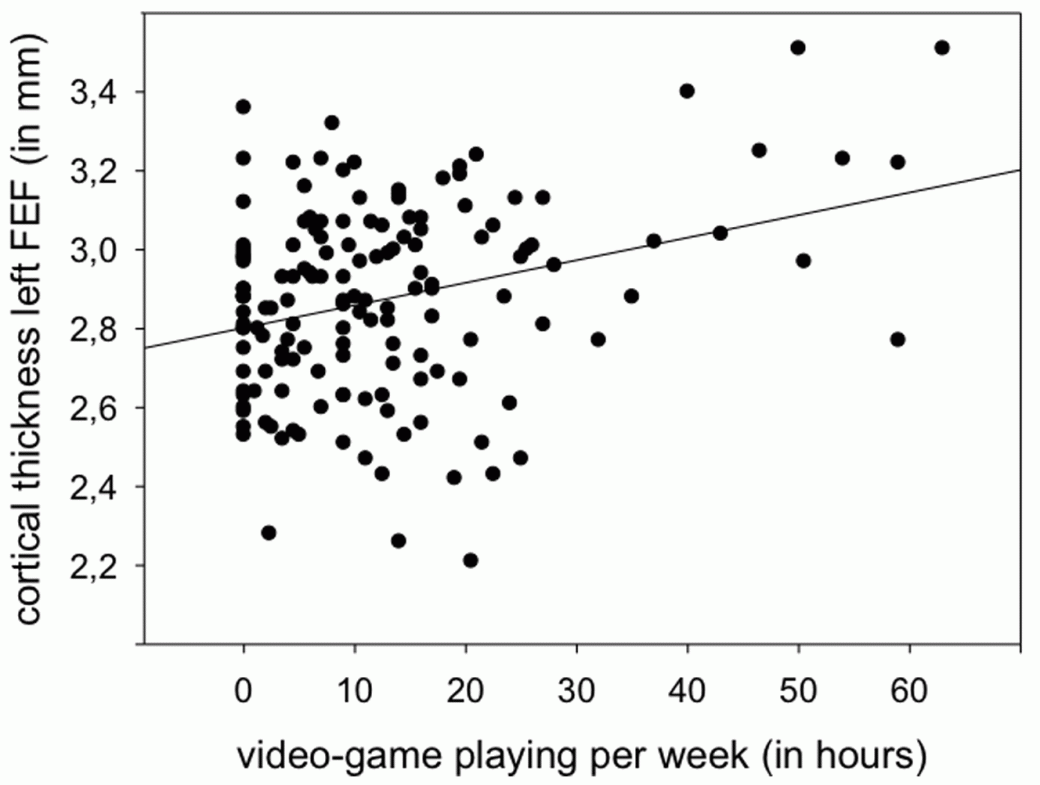

Европейские ученые исследовали мозг 152 подростков-игроков с помощью магнитно-резонансного томографа и программы FreeSurfer и обнаружили устойчивую связь между временем, проведенным за играми, и утолщением коры головного мозга. Их работа опубликована в журнале Plos One.

В эксперименте участвовали как юноши, так и девушки. С их слов они проводят за видеоиграми в среднем 12,6 часов в неделю (мужчины играют дольше женщин). Ученые заметили у игроков утолщение левой дорсолатеральной префронтальной коры головного мозга (DLPFC) и коры в зрительной области лобной доли слева (FEF) — в цитоархитектоническом поле Бродмана 8. При этом исследователи не обнаружили, что кора утончилась в какой-либо другой области.

Поскольку считается, что чем больше кора головного мозга, тем лучше работают мыслительные процессы, исследователи допускают, что нашли биологическое обоснование тому, что видеоигры благотворно сказываются на мозге. Впрочем, не исключено, что люди с развитой корой просто чаще предпочитают видеоигры. Чтобы разобраться в причинах и следствиях, нужно провести дополнительные эксперименты.